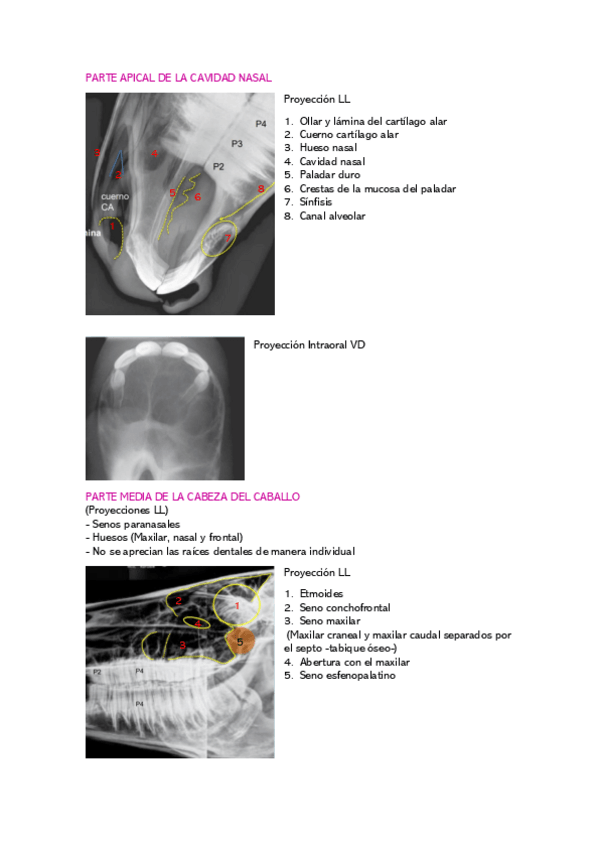

RADIOLOGIA-VIAS-RESP.-EQUIDOS.pdf